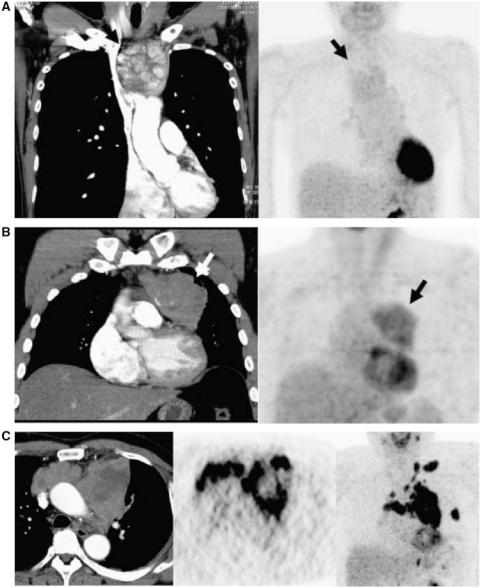

The role of [¹⁸F]fluorodeoxyglucose positron emission tomography in thymic epithelial tumors.

The purpose of this study was to systemically review the available literature regarding the diagnostic performance of positron emission tomography (PET) using 2-[18F]fluoro-2-deoxy-D-glucose ([18F]FDG) in patients with thymic epithelial tumors. We reviewed 13 studies that evaluated the diagnostic role of thymic epithelial tumors with [18F]FDG-PET. [18F]FDG-PET is a useful radiological modality for differentiating between thymomas and thymic carcinoma. However, [18F]FDG-PET may not be useful for differentiating low-risk thymoma and high-risk thymoma. One paper reported that [18F]FDG-PET has a predictive significance for treatment and prognosis in thymic epithelial tumors. Two papers reported that the degree of [18F]FDG uptake in thymic epithelial tumors is based on glucose metabolism. [18F]FDG-PET may have a further use for radiological differential diagnosis of thymomas and thymic carcinomas.